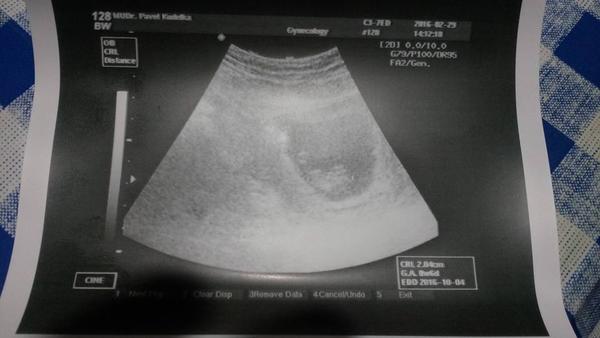

Ahoj holky čekáme s přítelem první miminko,dle poslední MS - 20.prosince bych měla být v 10+2 týden. Byla jsem včera na kontrole ale dle ultrazvuku jsem teprve 8+6 týden. Plod má 2,04cm viz foto. Já tam teda nevidím skoro nic :( je to celý šíleně zrnitý,a něco malinko tam jenvidím,když se dívám z dálky jinak ne.

Má to takhle vypadat??? Měli jste někdo stejný obrázek z ultrazvuku?

Doktor tvrdí,že je tam jeden živý plod ale srdíčko mi neukázal zda bije. Mám přijíd až za 4 týdny.

ahoj, neboj se, určitě je to v pořádku, mám to dost podobné, na ultrazvuku jsem byla ve stejný čas jako ty, podle menstruace dokonce 11plus2, podle ultrazvuku 8plus2. takže tři týdny mimo. asi byla později ovulace, to se stát může. taky mě pozvali až za 4 týdny. jestli ti doktor řekl, že je tam živý plod, tak určitě srdíčko tlouklo, jen tě na to neupozornil a neukázal ti ho. a obrázek mám podobný 🙂

Tak pokud je vidět srdíčko, tak bych se nestresovala. Prostě se to někdy může stát že byla ovu později, to počítání dle utz počítá s tím, že jí máš přesně uprostřed MS, ale můžeš ji´klidně mít dřív a nebo naopak později. Jinak co se týče snímki, kvalita záleží na daném přístroji a hlavně teď opravdu ještě na těch snímcích není nic moc vidět, já měla ze 7+2tt a teda bylo to taky takové zrnité cosi ale neboj, ze screeningu ve 12tt budeš mít už krásný obrázek a budeš see sama divjt jak se za ten měsíc z toho rozmazaného "cosi" stalo malilinkaté miminko.. Přeji hodně štěstí